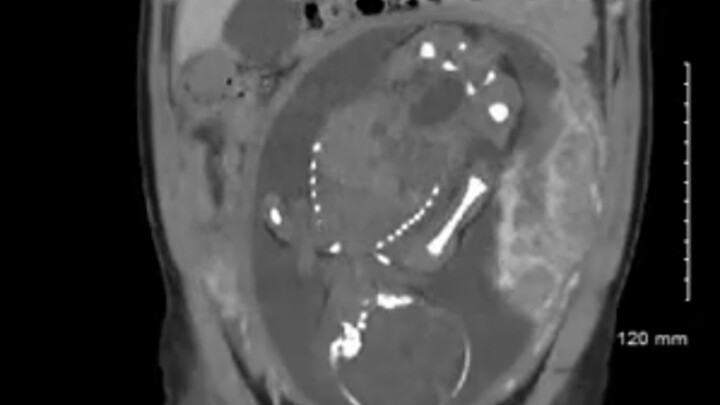

كيف سيبدو كيس يفوق حجمه كرة السلة عند فتحه؟

امرأة تبلغ من العمر 25 عامًا تأكل كميات كبيرة من الشعر، اكتشف كيفية إخراجه